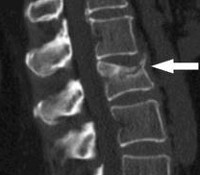

Всем больным с переломами позвонков назначают рентгенографию поясничного отдела позвоночника в двух проекциях. Наиболее информативен боковой снимок, на котором выявляется снижение высоты передних отделов позвонка. Для оценки состояния нервных структур пациентов направляют на консультацию к нейрохирургу или неврологу. Используют МРТ позвоночника, позволяющее выявить наличие или отсутствие и степень повреждения нервных структур. При необходимости проводят КТ позвоночника, электрофизиологические исследования, миелографию и ликвородинамические пробы.

Диагноз устанавливается на основании характерного анамнеза, симптомов и результатов рентгенографии позвоночника. Снимки выполняются в двух проекциях, наиболее информативна боковая проекция. На рентгенограмме выявляется снижение высоты и клиновидная деформация одного или нескольких позвонков. При необходимости для оценки состояния спинного мозга и его оболочек, а также связок и хрящей позвоночника, назначают МРТ или КТ позвоночника. При наличии неврологических нарушений больного направляют на консультацию к неврологу или нейрохирургу. Для выявления и более точной оценки степени повреждения спинного мозга применяют миелографию.

Диагностика